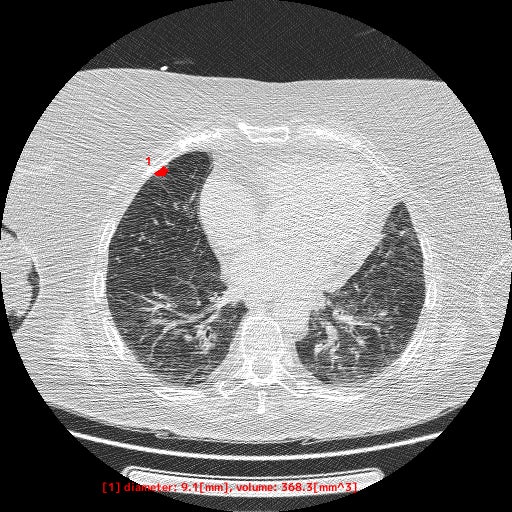

本製品は、胸部CT画像から肺野領域の組織について、使用者が設定した基準値に基づくCT値から「関心領域」を抽出し、その体積と最大径を自動計測します。計測した最大径が閾値以上となった場合には、画像上に色付けして表示します。この抽出・計測・表示機能は、医師が胸部CT画像を対象に読影診断を行う際に併用することで、肺野周辺組織とCT値が異なる肺結節等の視認性向上に寄与することが期待されます

【EIRL Chest CTによる表示例】

① 標準線量CT